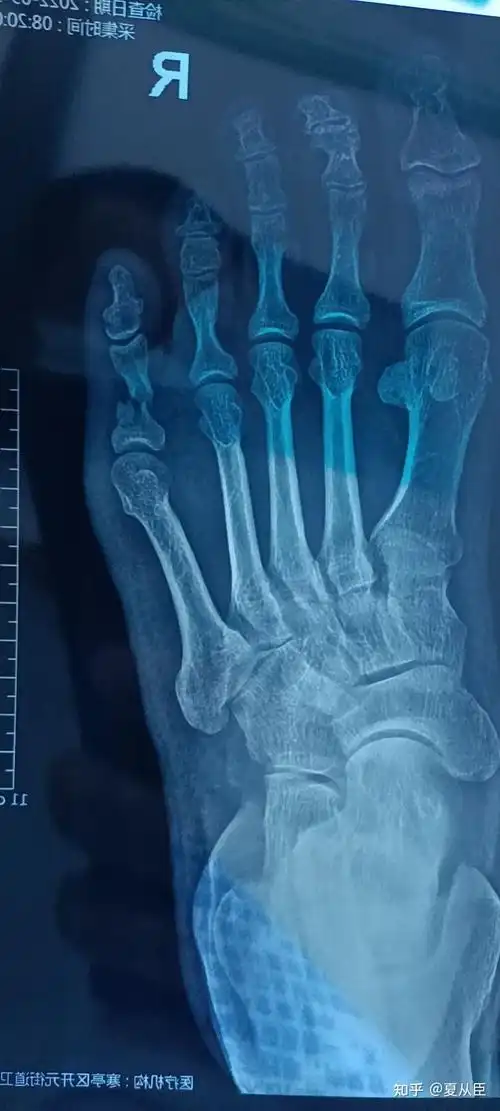

第三脚趾骨折,打入钢钉后两周,有几个问题咨询?